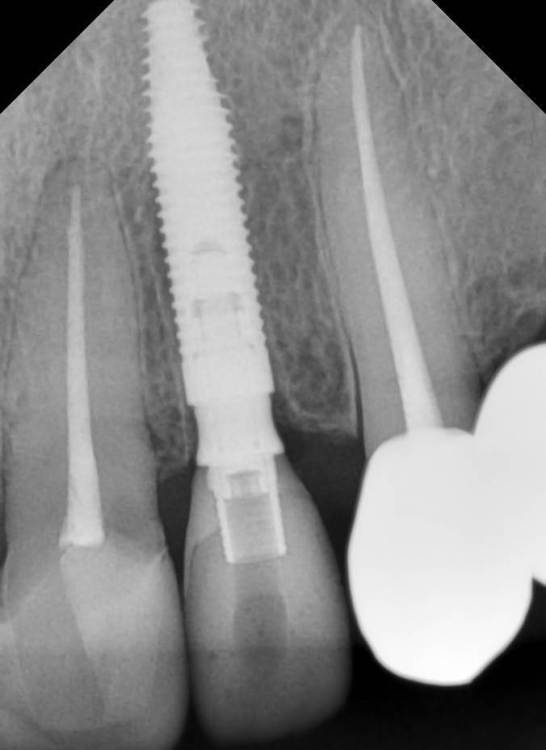

kramer Опубликовано 7 февраля, 2022 Поделиться Опубликовано 7 февраля, 2022 Я кстати в последнее время для одномоментной имплантации во фронте люблю использовать 15 или 16 мм имплантаты. Такая длина в сочетании с мало-мальским торком улучшает мой сон. Неодент 3,5х16, зуб 22 + коронка 1 1 Ссылка на комментарий